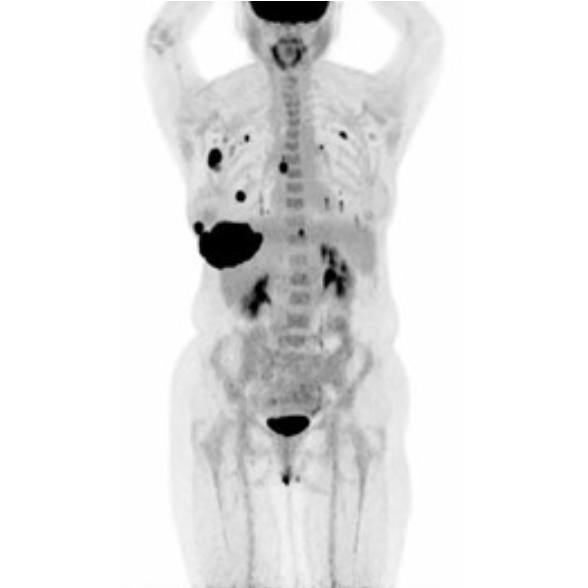

Partial nml and melanoma PET scan

The use of PET/CT in oncology assists physicians in answering clinical questions such as:

The goal of PET/CT imaging in oncology is to enable the physician to distinguish between benign and malignant pathologies, to determine the extent of disease, to detect residual and recurrent tumors, to monitor the effectiveness of treatments, and to guide therapies.